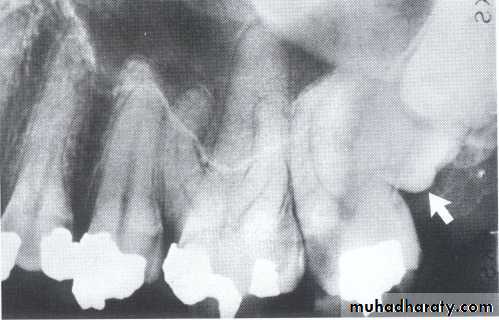

Dilacerated root. The apical portion of the root is bent buccally or lingually into the plane of the central ray. Note the halo in the apical region, produced by the PDL

space (arrow).